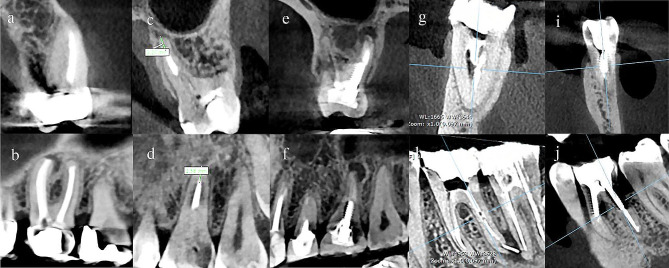

The data from independent variables recorded by the examiner were as follows: tooth number, gender, jaw type, the status of missed canals and their quantity, obturation material length, type of restoration, presence of a separated instrument, presence of a post/screw in the canals, presence of perforation (Fig. 1). Length of obturation was classified as appropriate if the ending was at a distance of 0–2 mm from the apex, underfilled when it was shorter than 2 mm from the apex, and overfilled if the material extruded the apex [ref. 3].

Data on the four dependent variables were recorded: presence of PL, PL volume, presence of CBD, and BPBH. PL was identified as absent when intact periapical bone structures could be detected (diameter of the periapical radiolucency under 0.5 mm), and otherwise as present [ref. 25]. In order to evaluate PL volume, the tooth was viewed in the sagittal plane with one-millimeter interslice intervals. The surface area of the PL in each slice was measured using the area tool in the software (Fig. 2). Considering the PL as an asymmetrical 3D object, its volume was measured using the formula presented below, where h represents the interslice interval, and S denotes the surface area of partial frustum bases. The accuracy of this measurement method has been proven in several publications [ref. 18, ref. 26, ref. 27].